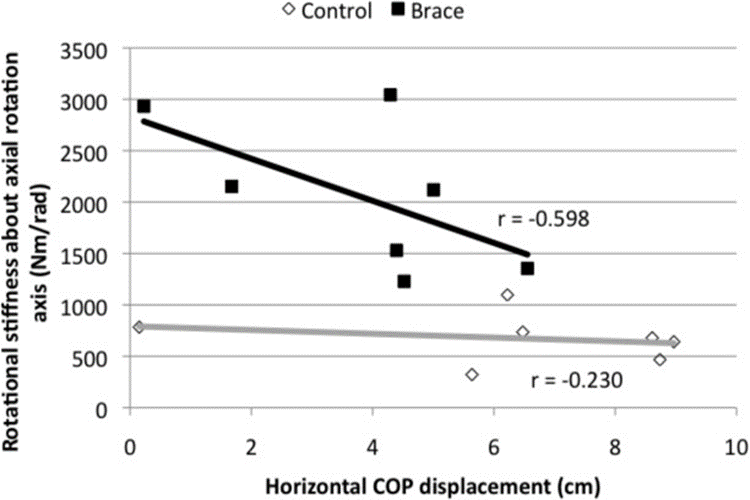

이와 연관하여 2009년도에 나온 크레이그 리벤슨 선생님의 논문에서는

Abdominal bracing은 능동적인 다리 거상 레그레이즈를(Active Straight Leg Raise Test of

Mens (Liebenson et al.2009) 하는 동안 허리의 축회전강직 (Axial Rotation Stiffness)통한

척추의 견고함을 증가시키고 Active Straight Leg Raise test동안에 척추의 불안정성을

만들수있는 축회전(Axial Rotation)을 감소시킬수 있다라고 언급하였습니다.

(Liebenson et al., 2009)